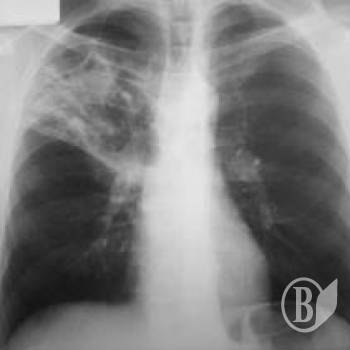

Захворюваність серед постраждалих у 2012р. становила 71,8 тис. випадків уперше встановлених діагнозів на кожні 100 тис. осіб, що перебували на обліку. Найбільш розповсюдженими були хвороби органів дихання (36,1 тис. випадків), системи кровообігу (5,6 тис.), шкіри і підшкірної клітковини (4,3 тис.), кістково-м’язової системи та сполучної тканини (4,0 тис.), сечостатевої системи (3,5 тис.) тощо.